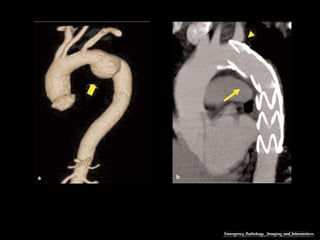

Ruptura: extravazamento do contraste e hemotórax

Haaga JR, Dogra VS, Forsting M, et al. TC e RM uma abordagem do corpo humano completa. Editora Mosby-Elsevier,

2009.